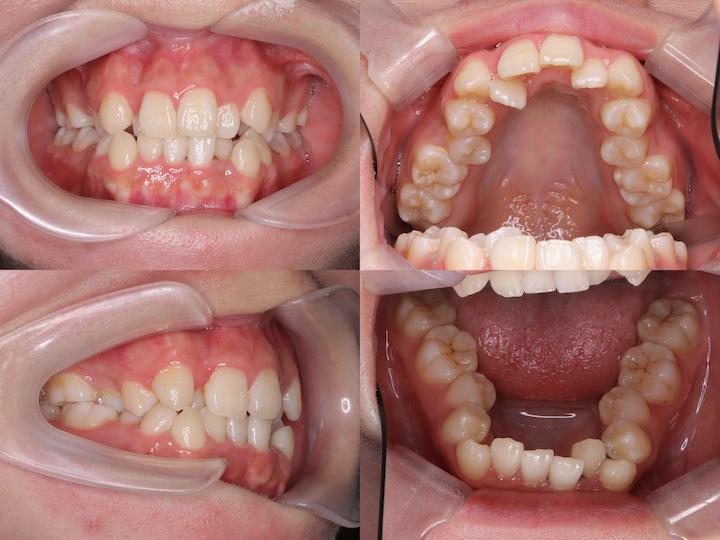

本症例は、上下顎前歯部の著しい叢生および犬歯の低位唇側転位(八重歯)を主訴とする患者様に対し、上下顎ともに舌側矯正装置を使用して治療を行いました。

高度なアーチレングスディスクレパンシーを改善するため、上下小臼歯の計4本を抜歯し、適切な咬合関係の確立を図りました。

また、AngleⅡ級臼歯関係の改善を目的として、下顎大臼歯を近心移動する治療計画を採用しました。

主訴:上下前歯部の叢生および犬歯の低位唇側転位(八重歯)

初診時の口腔内所見として、以下の不正咬合が認められました。・上下顎前歯部の重度叢生

・犬歯の低位唇側転位(八重歯)

・著しいアーチレングスディスクレパンシー

・AngleⅡ級臼歯関係(下顎大臼歯の後方位)

・口唇部の突出感は認められない